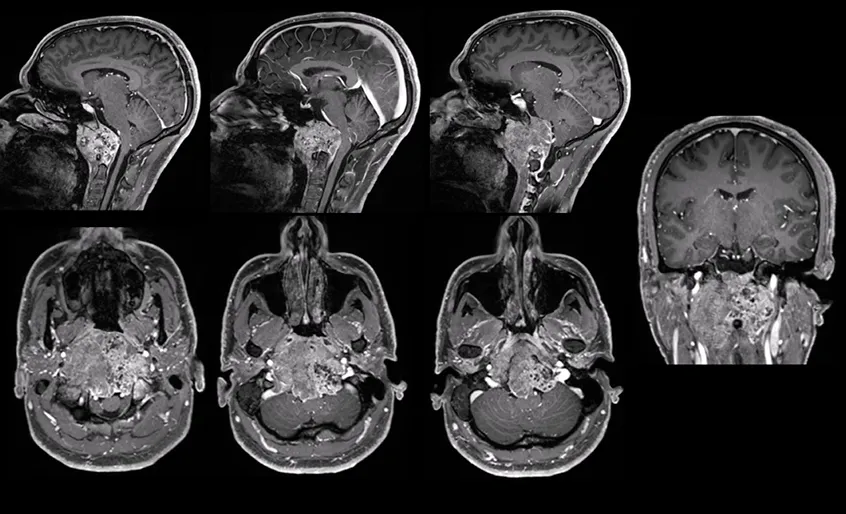

一名45岁的男士被发现有颅颈交界区脊索瘤后,福洛里希教授为他进行的是开颅手术,同时辅以内窥镜探查,肿瘤得以完整切除,无其他并发症。

使用前外侧入路的开颅手术的说明性案例。左侧图像:术前MRI显示颅颈交界区脊索瘤包裹左侧椎动脉硬膜内部分(箭头)。中间图:从右侧显示手术入路的示意图,以及从左侧椎动脉逐步剥离肿瘤的术中图像,在手术结束时内镜下可以看到两个保存完整的椎动脉。右图:术后MRI显示肿瘤完全切除,左侧椎动脉通畅(箭头)。